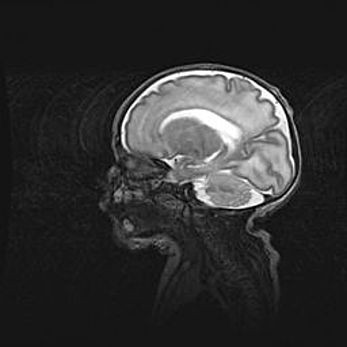

Мальформация Денди-Уокера. Киста задней черепной ямки.

Агенезия мозолистого тела.

Возраст: 2,5 месяца

Вес: 2420 г

Пол: женский

Окружность головы: 37 см

Срок гестации: 32 недели

Мальформация Денди—Уокера — редкий вид патологии ЦНС, представляющий собой врожденный порок развития каудального отдела ствола и червя мозжечка, ведущий к неполному раскрытию срединной (Мажанди) и латеральных (Лушка) апертур IV желудочка мозга. Для этогно синдрома характерна триада симптомов: гипотрофия червя мозжечка и/или полушарий мозжечка, кисты задней черепной ямки, гидроцефалия различной степени. В 70% случаев порок сочетается и с другими аномалиями головного мозга, в частности с агенезией мозолистого тела.